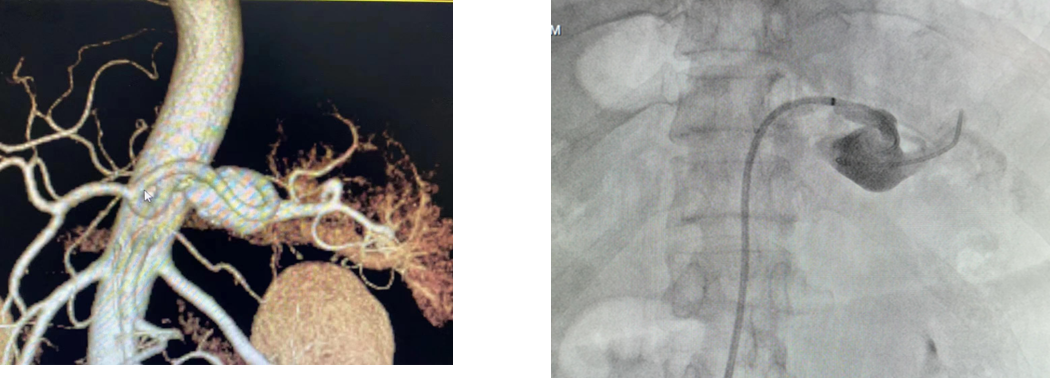

病例1 动脉瘤栓塞

病例2 分支栓塞+瘤腔栓塞

病例3 瘤腔栓塞加胶填充

病例4 两端栓塞+瘤腔填塞

病例5 多发动脉瘤分支+主干栓塞

图为:分支栓塞

图为:主干栓塞最后造影